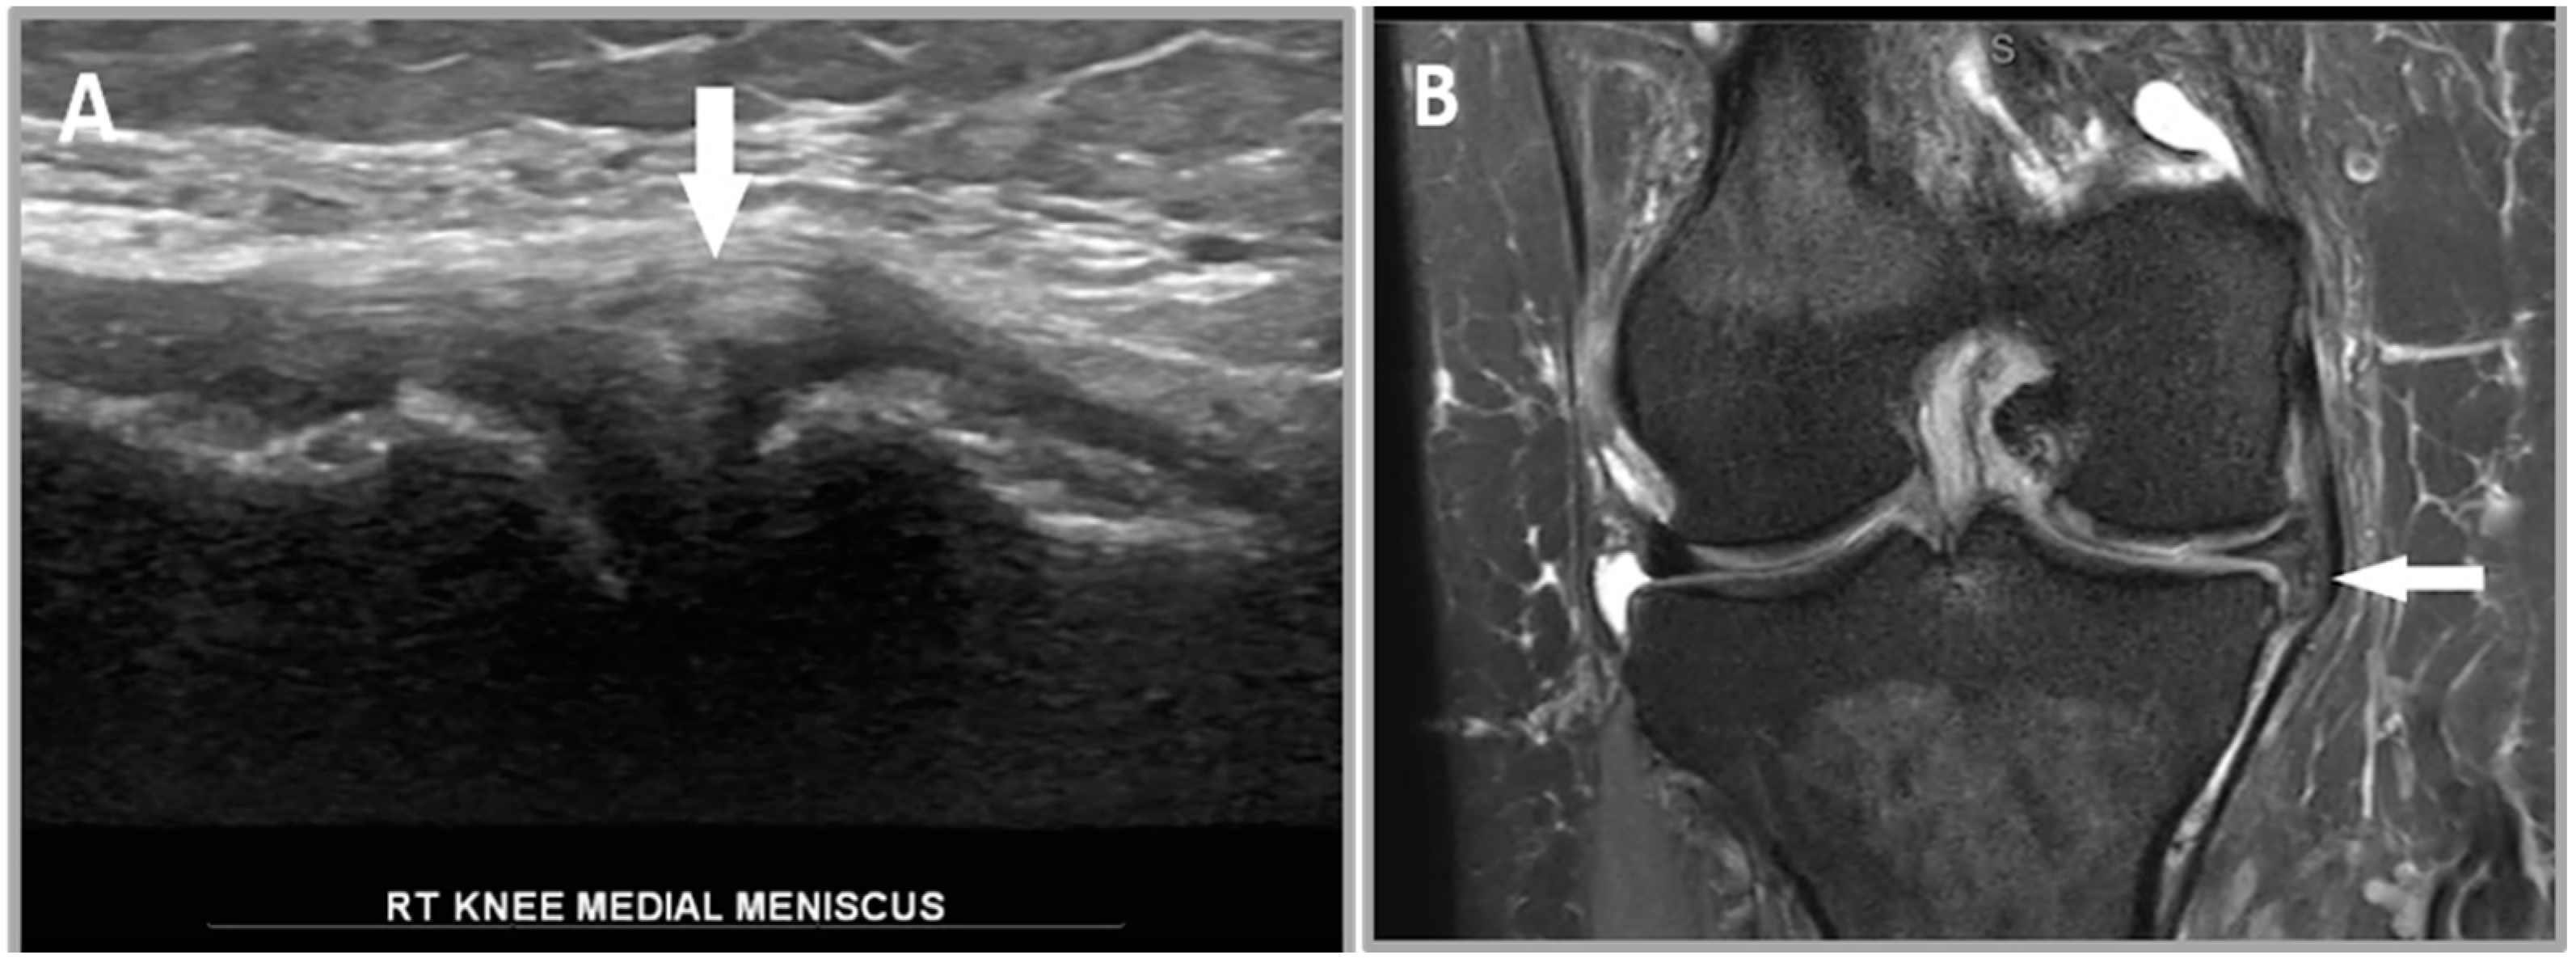

2.5.3. Criterion 3—Diminutive Meniscus